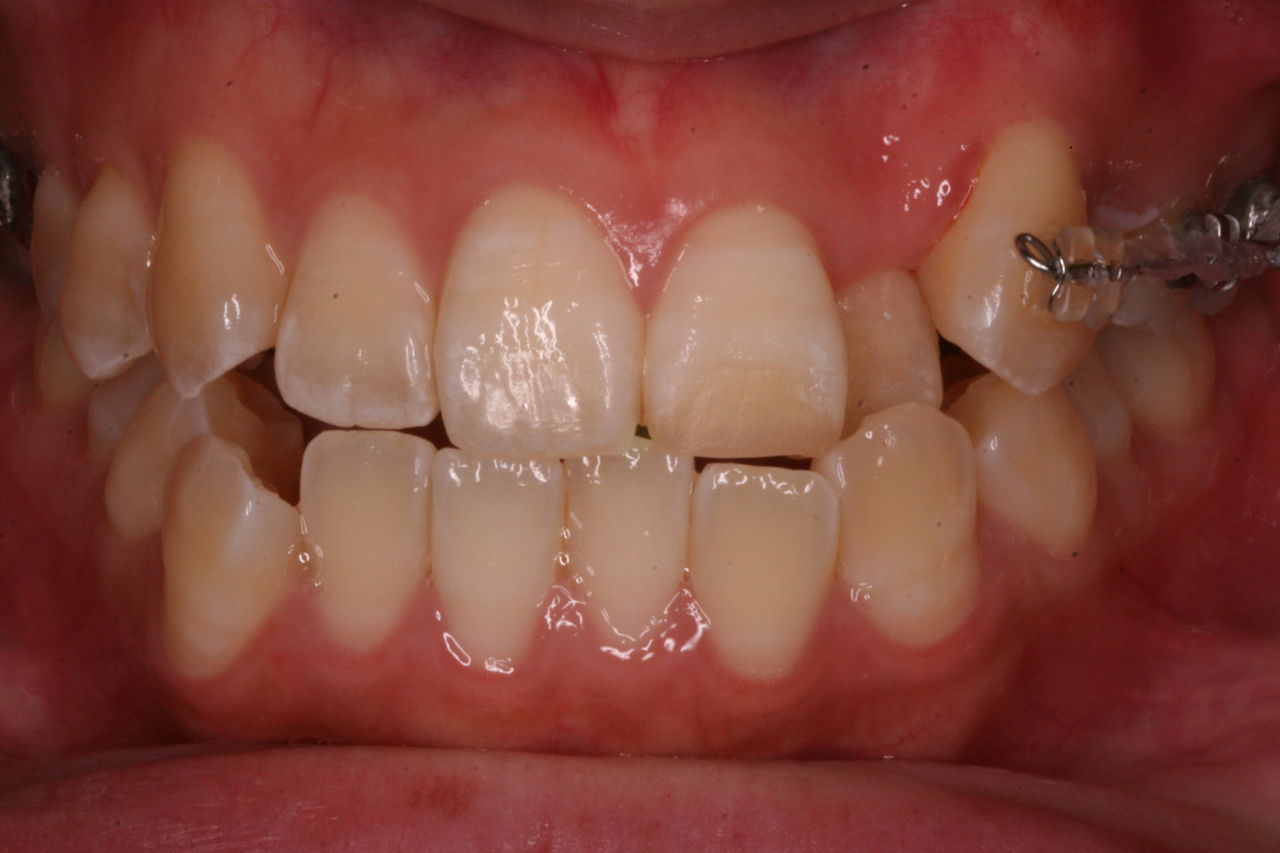

私の場合、治療開始時から全部つけるのをあまり好みません。必要な部分のみ装置をセットすることが多いいです。

治療終了時です。

初診の状態と比較していただければ、仕上がりの状態がより理解できると思います。